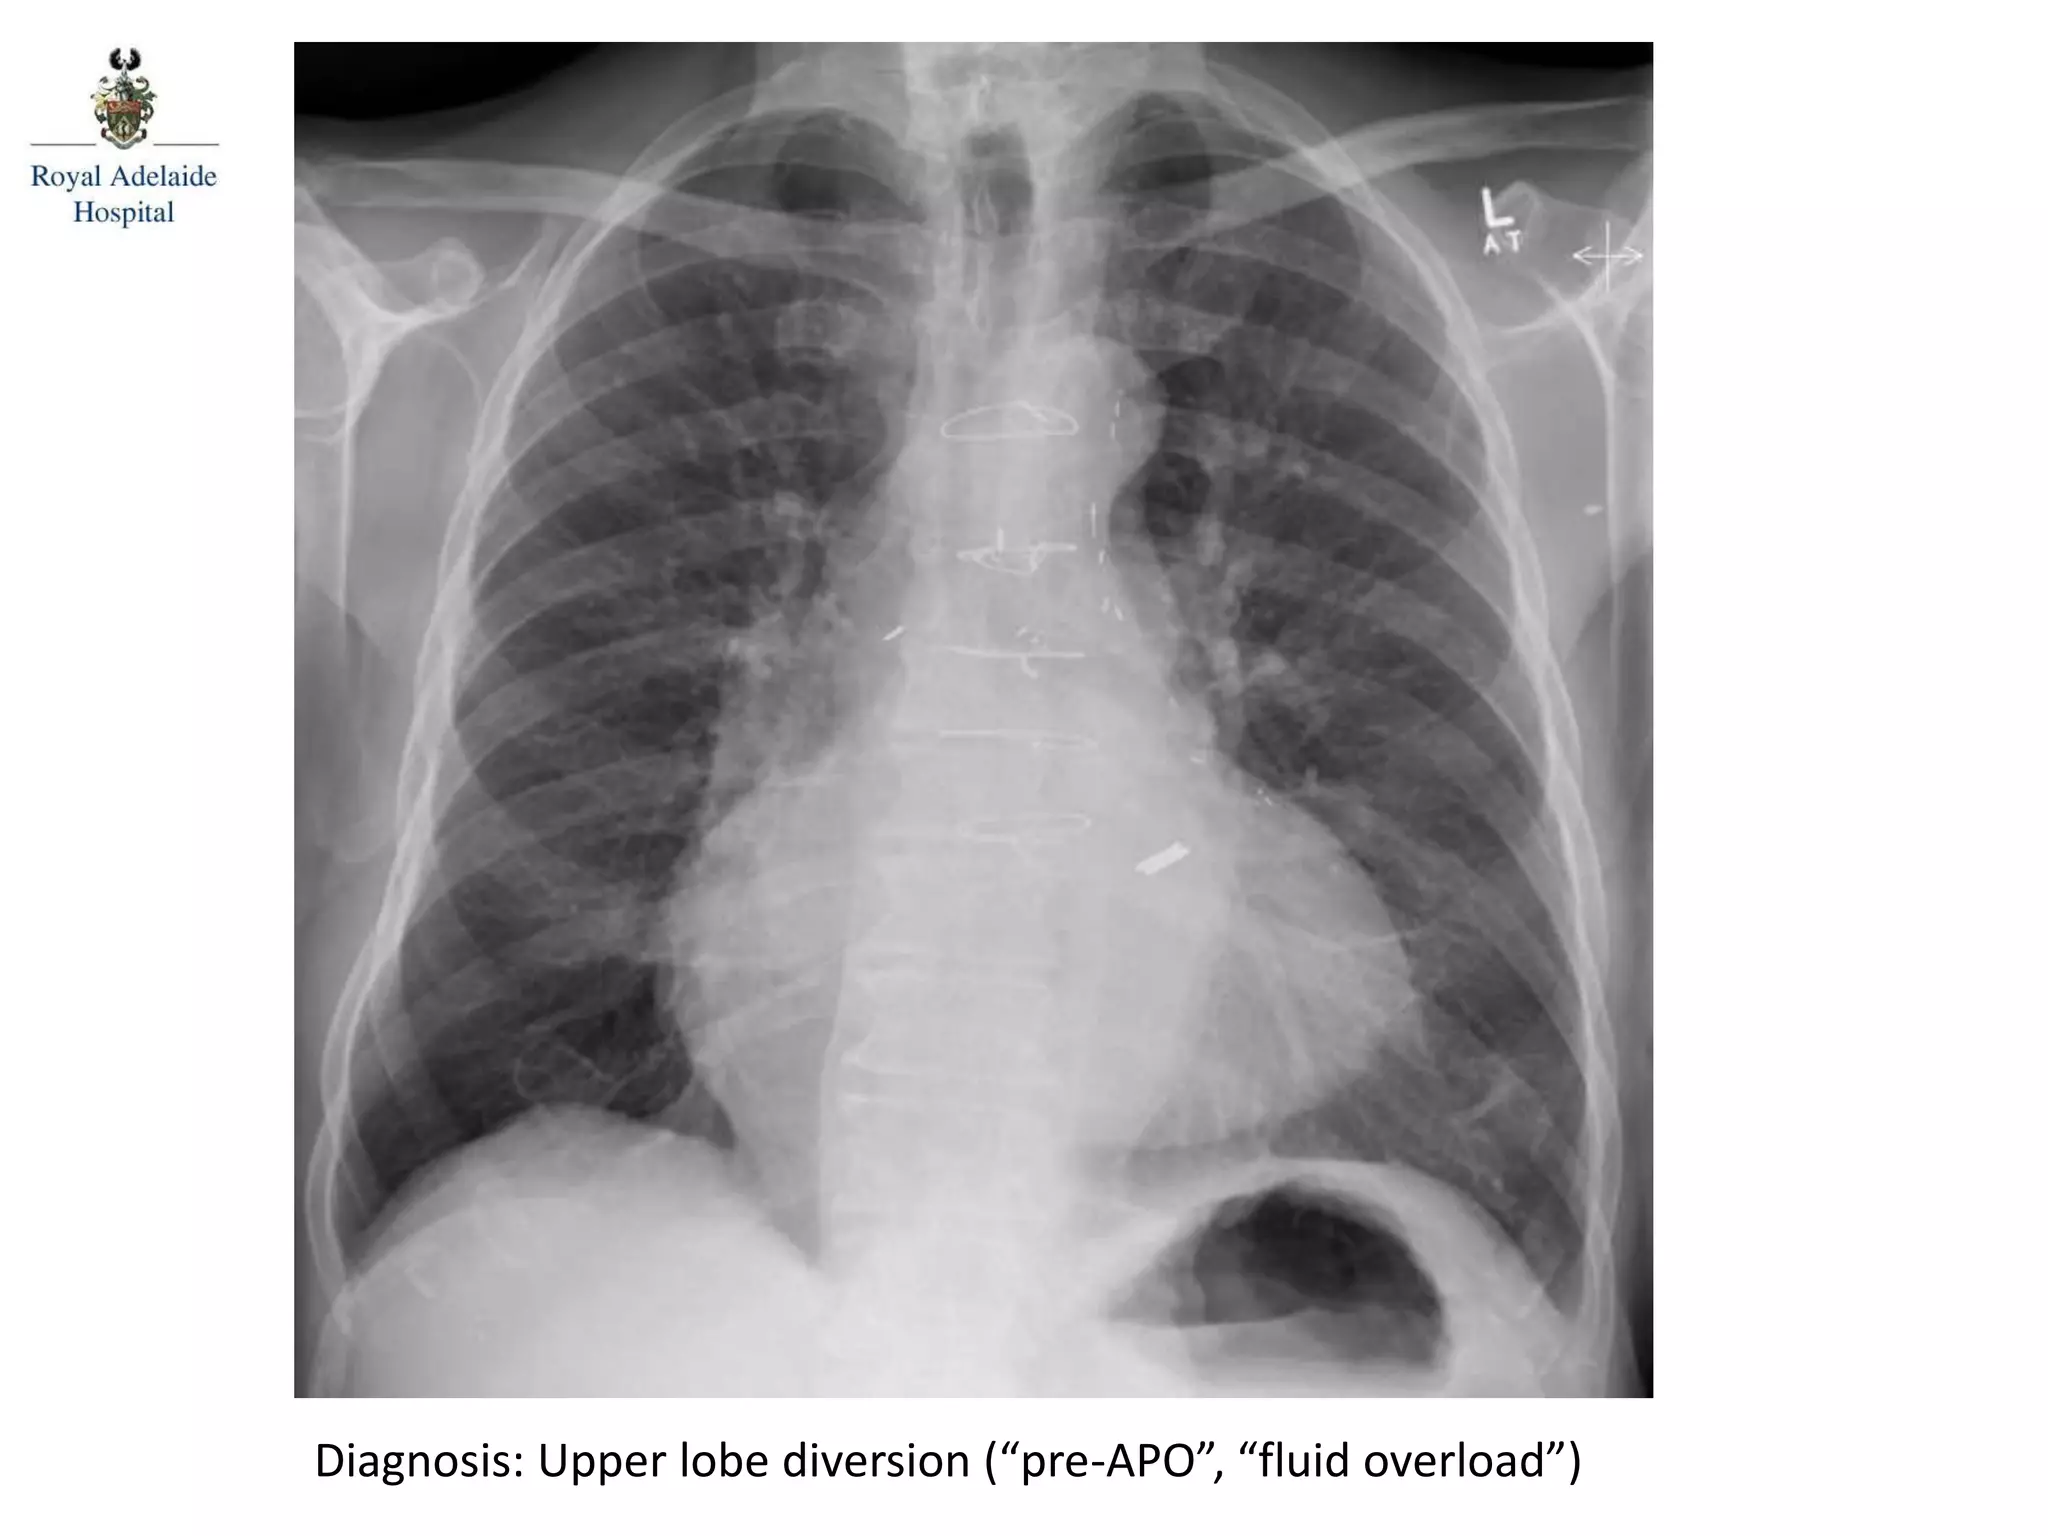

Diagnosis: Upper lobe diversion (“pre-APO”, “fluid overload”)